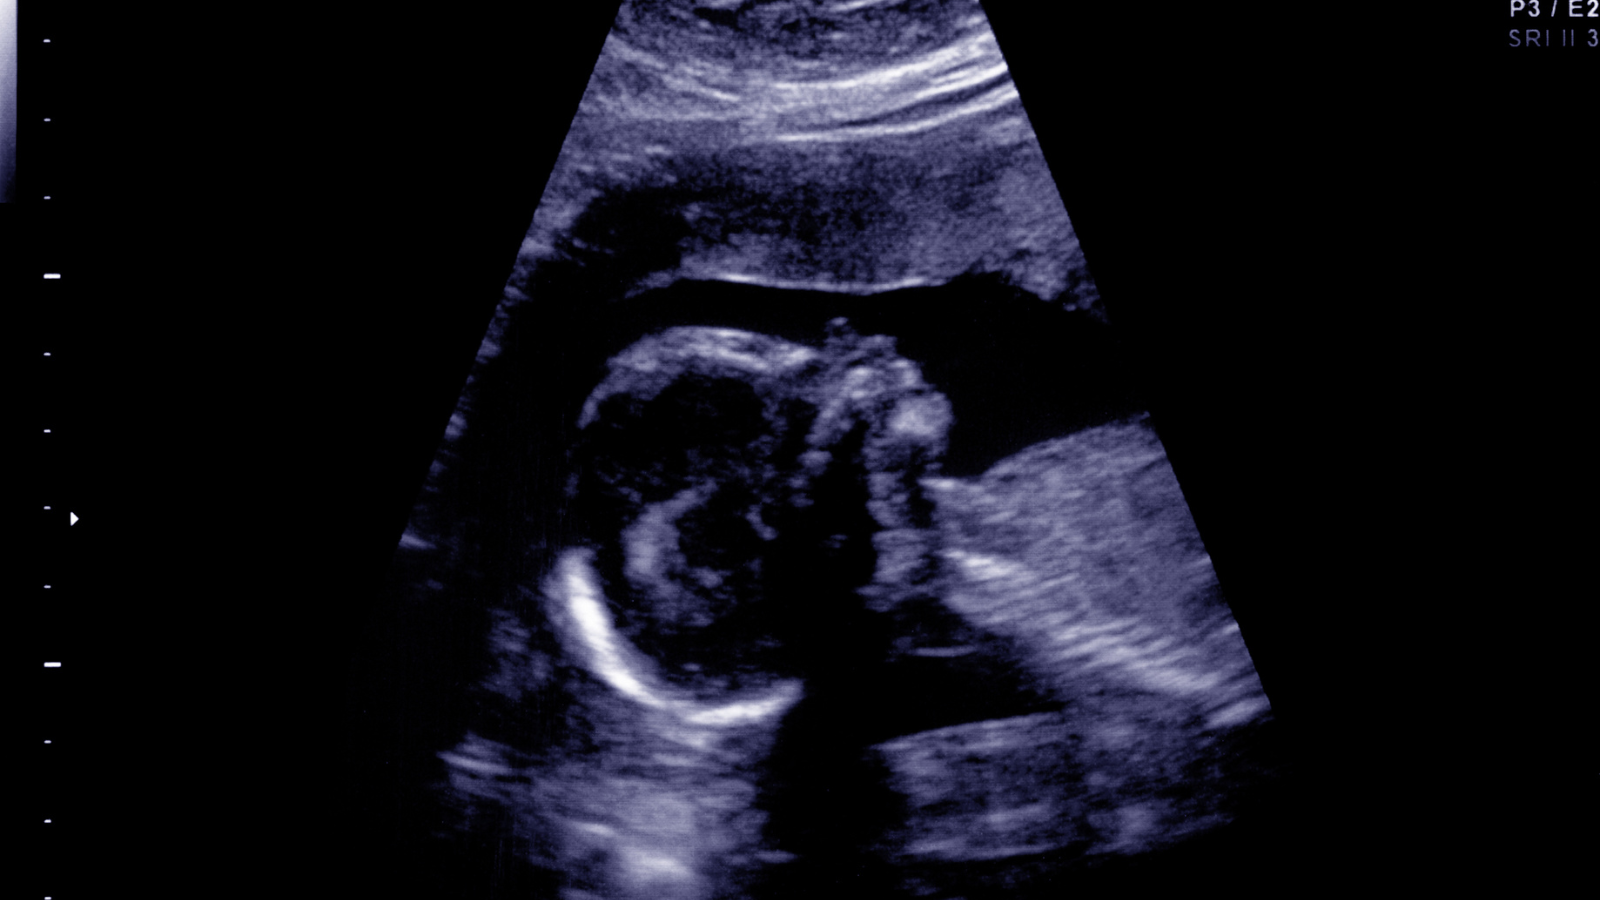

Việc đánh giá mức độ giãn não thất có ý nghĩa quan trọng trong tiên lượng và xây dựng kế hoạch theo dõi, chăm sóc thai kỳ. Do đó, mẹ bầu cần thực hiện siêu âm định kỳ, đồng thời tuân thủ hướng dẫn từ bác sĩ chuyên khoa để có biện pháp xử trí phù hợp.

Để chẩn đoán giãn não thất, bác sĩ thường kết hợp nhiều phương pháp. Trong đó, xét nghiệm nồng độ AFP giúp phát hiện sớm nguy cơ bất thường nhiễm sắc thể. Phương pháp siêu âm thai kỳ và kỹ thuật chọc ối cũng được sử dụng nhằm xác định chính xác tình trạng giãn não thất và các dị tật đi kèm.

Trong trường hợp siêu âm phát hiện giãn não thất dưới 10mm ở tam cá nguyệt thứ hai, mẹ bầu không nên quá lo lắng. Đây thường là tình trạng nhẹ và có thể chỉ là biểu hiện thoáng qua. Thai phụ cần được thăm khám định kỳ để theo dõi mà không cần can thiệp đặc biệt ngay lập tức. Giãn não thất mức độ nhẹ đôi khi xuất hiện do ảnh hưởng của các dị tật khác, vì vậy bác sĩ sẽ tiến hành kiểm tra kỹ hơn, bao gồm siêu âm tim và não để loại trừ bất thường.